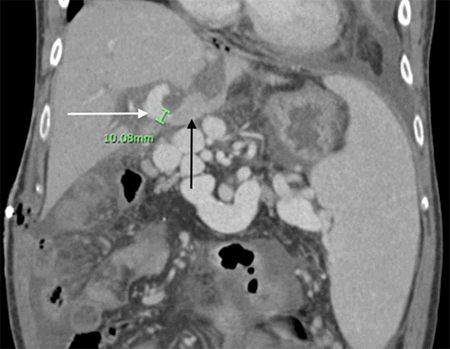

Preoperative CT demonstrated main portal vein dilated to 1.9 cm with a completely occlusive thrombus that extended to the left and right portal vein with cavernous transformation, consistent with grade IV PVT (Figure 1 and Figure 2).

Figure 1. Illustration Depicting PVT with Dilated Left Gastric Vein (Black Arrow). Published with Permission

A large dilated left gastric vein was noted. Additionally, periesophageal, perigastric, perisplenic, and mesenteric varices were present with moderate ascites and splenomegaly. Due to the PVT extending to the confluence of superior mesenteric vein (SMV), an abdominal ultrasound was performed to evaluate the left gastric vein flow for possible left gastric-portal anastomosis. Ultrasound showed a patent left gastric vein dilated to 2 cm in the mid-epigastrium with phasic variations (Figure 3) with an average velocity of 42.1 cm/sec. Given the sufficient size and flow of the patient’s left gastric vein, a surgical plan for gastric-portal anastomosis for liver allograft inflow was pursued.